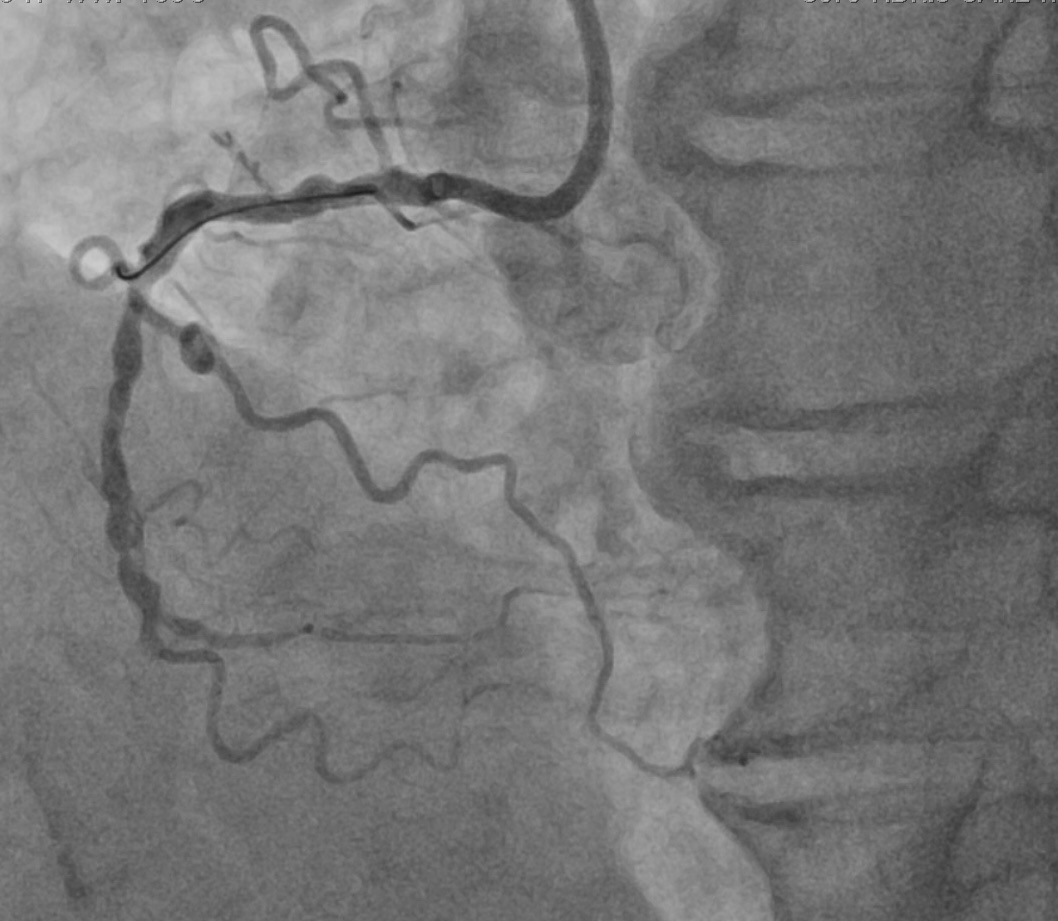

A 58 years old man with background of hypertension was referred to our unit for activity limiting angina refractory to medical treatment. Coronary angiogram showed severe triple vessel disease with a distal right coronary artery (dRCA) total occlusion. Echocardiogram showed normal LVEF with no regional wall motion abnormality. He was counselled on revascularization for symptom control and opted for multivessel PCI over CABG as the definitive treatment.

Relevant Catheterization Findings

A 7Fr AL 0.75 guiding catheter was engaged to RCA. dRCA CTO was successfully crossed with a Fielder XTR (Asahi) wire on Turnpike (Teleflex) microcatheter support, exchanged to a Runthrough NS (Terumo) wire and wired to the RPL. The CTO segment was predilated with 2mm semi-compliant ballon with restoration of TIMI 2 flow to RPL.